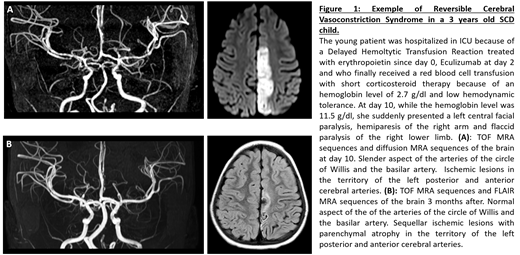

25 strokes occurred during the study period. 12 of them (48%) did not met the definition of a "typical" stroke related to sickle cell CV. The children with "atypical" stroke were older (9 years old +/- 4.6, vs 6.5 years old +/- 4.3 in the typical group, p = 0.0086) and less frequently of SS genotype (33% non-SS vs 8% non-SS in the typical group). They had lower leukocyte count (11.3 G/L +/- 4.6, vs 15.7 G/L +/- 2.3 in the typical group, p=0. 04) and higher hemoglobin level at the time of the stroke (11 g/dl +/- 3 vs 7.4 g/dl +/- 1.3 in the typical group, p= 0.027). 17% of atypical strokes had posterior ischemic lesions, 33% had anterior lesions and 17% had multiple systematized lesions, in counting junctional lesions. We also found 33% of ischemic lesions of the cerebellum. Considering a potential trigger of the stroke, 58% of atypical events were hospitalized in an anesthesia or intensive care unit at the time of the stroke or less than 7 days before, compared to 8% of children with a "classic" stroke (p= 0.011). The etiologies adopted by clinicians and radiologists for the atypical stroke were reversible cerebral vasoconstriction syndrome (RCVS) (Figure 1), cerebral fat embolism, hyperviscosity and vasculitis in systemic inflammatory context. The evolution in the atypical group was more favorable in terms of recurrence (0% within 2 years vs 42 % in the typical group, p= 0.045), although only 33% (3 children) of atypical strokes were still under exchange transfusion program 24 months after the stroke vs 92% in the group of typical stroke.

Overall, in a cohort of SCD children with efficient stroke prevention program, atypical strokes account for nearly half of all acute ischemic neurological events, related to hyperviscosity, RVCS or inflammatory vasculitis. Physicians must be aware of the potential triggers and of the context in which such events occur. Nevertheless, stroke without CV may not require long-term transfusion program contrary to stroke with CV, given the very low risk of recurrence we highlighted.